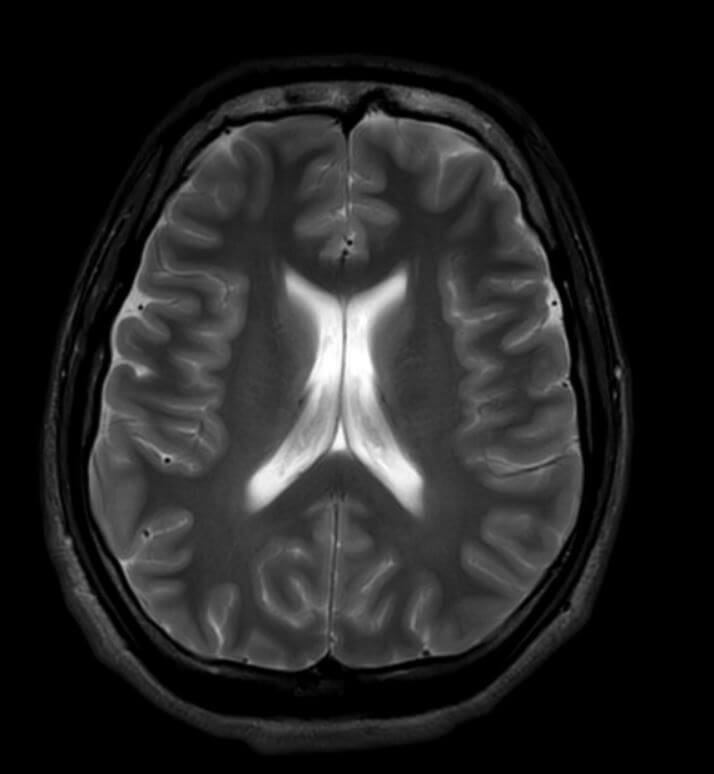

MRI

An MRI scan, or magnetic resonance imaging scan, is a non-invasive medical imaging test that uses a strong magnetic field and radio waves to create detailed images of the inside of the body.